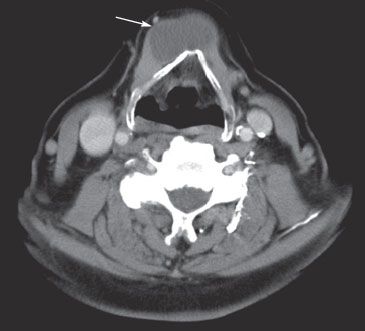

For several years, an asymptomatic, firm, nontender mass had been growing on the neck of a 54-year-old-man, slightly left of midline at the level of the hyoid bone. The mass was mobile on protrusion of the tongue and during swallowing. Thyroid function tests were normal. An axial thoracic CT scan was obtained.

What does it indicate?